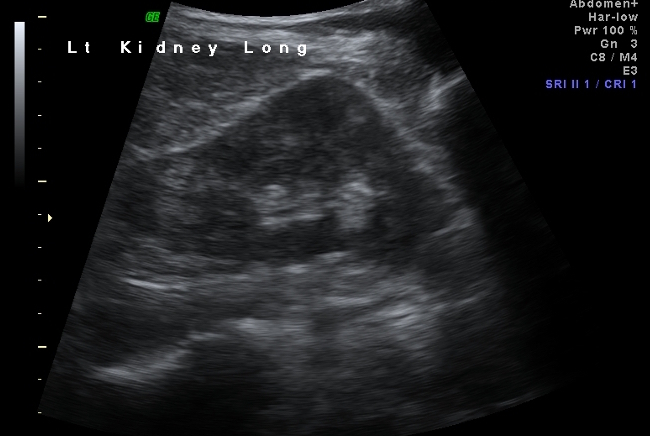

19F Hypertensive

kypokalaemia

elevated aldosterone

Juxtaglomerular Tumor (Reninoma)

Reninoma is a tumour of the cells of the juxtaglomerular apparatus that produces excessive amounts of renin, resulting in a secondary form of hyperaldosteronism, manifesting clinically with hypertension (HT) and hypokalaemia1. This renal tumour is predominant in females, with a peak incidence between the second and third decade of life and, although uncommon, it is a treatable cause of HT2. It should be suspected in any patient with refractory HT associated with hypokalaemia and high levels of aldosterone.

We present the first case of reninoma reported in Argentina in a young woman with refractory HT and hypokalaemia.

In 1967, Robertson et al.6 reported the first renin-producing tumour. Kihara et al. later called them “juxtaglomerular cell tumours”7. These tumours are very uncommon, with their incidence peaking between the second and third decade of life and they are predominantly found in females, originating in the myoendocrine cells of the renal juxtaglomerular apparatus, although the production of renin by different tumours has also been demonstrated, such as Wilms tumours, carcinoid tumours, renal oncocytoma and renal cell carcinoma8,9. In accordance with the presence or absence of symptoms, JCT may occur as: a “typical” variant in the majority of cases and manifests with HT, hypokalaemia, high plasma renin and secondary hyperaldosteronism; an “atypical” variant, in which HT is not accompanied by hypokalaemia; and a third “non-functioning” variant, which occurs without HT and with normal levels of potassium10,11.

Plasma renin activity (PRA) and plasma aldosterone (PA)